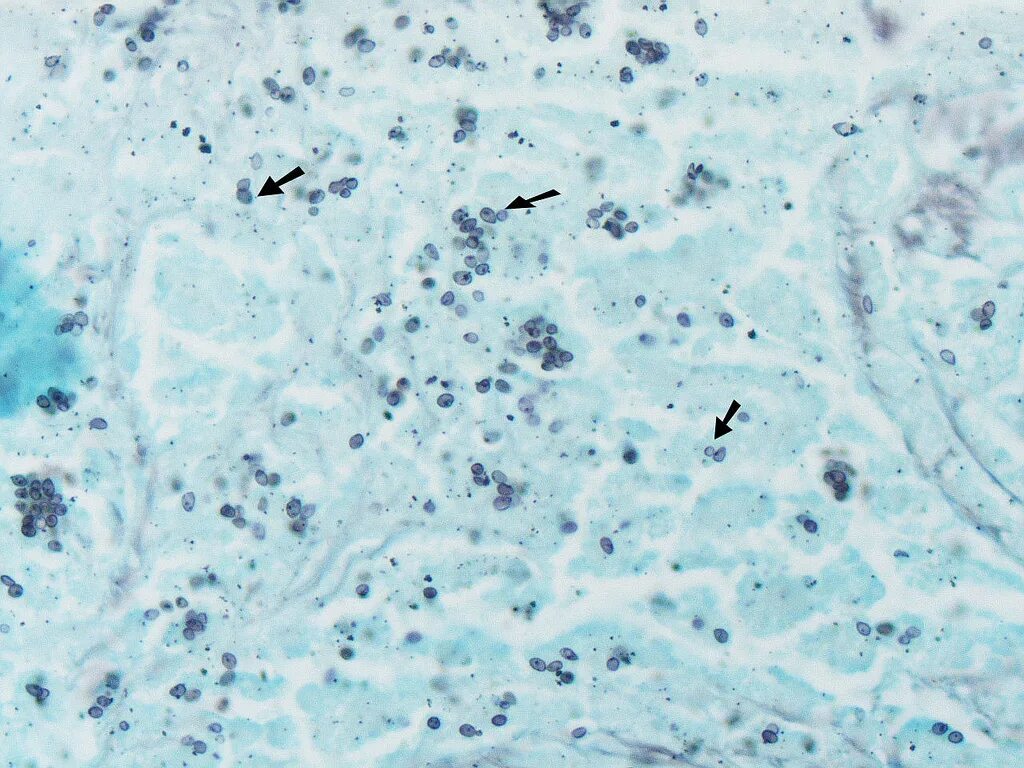

Гистоплазмоз это